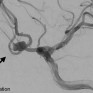

في الأحساء.. نجاح علاج تشوه قلبي مركب بالقسطرة لأول مرة بالمملكة

الواحة نيوز

8:01 م - 21 أكتوبر، 2025